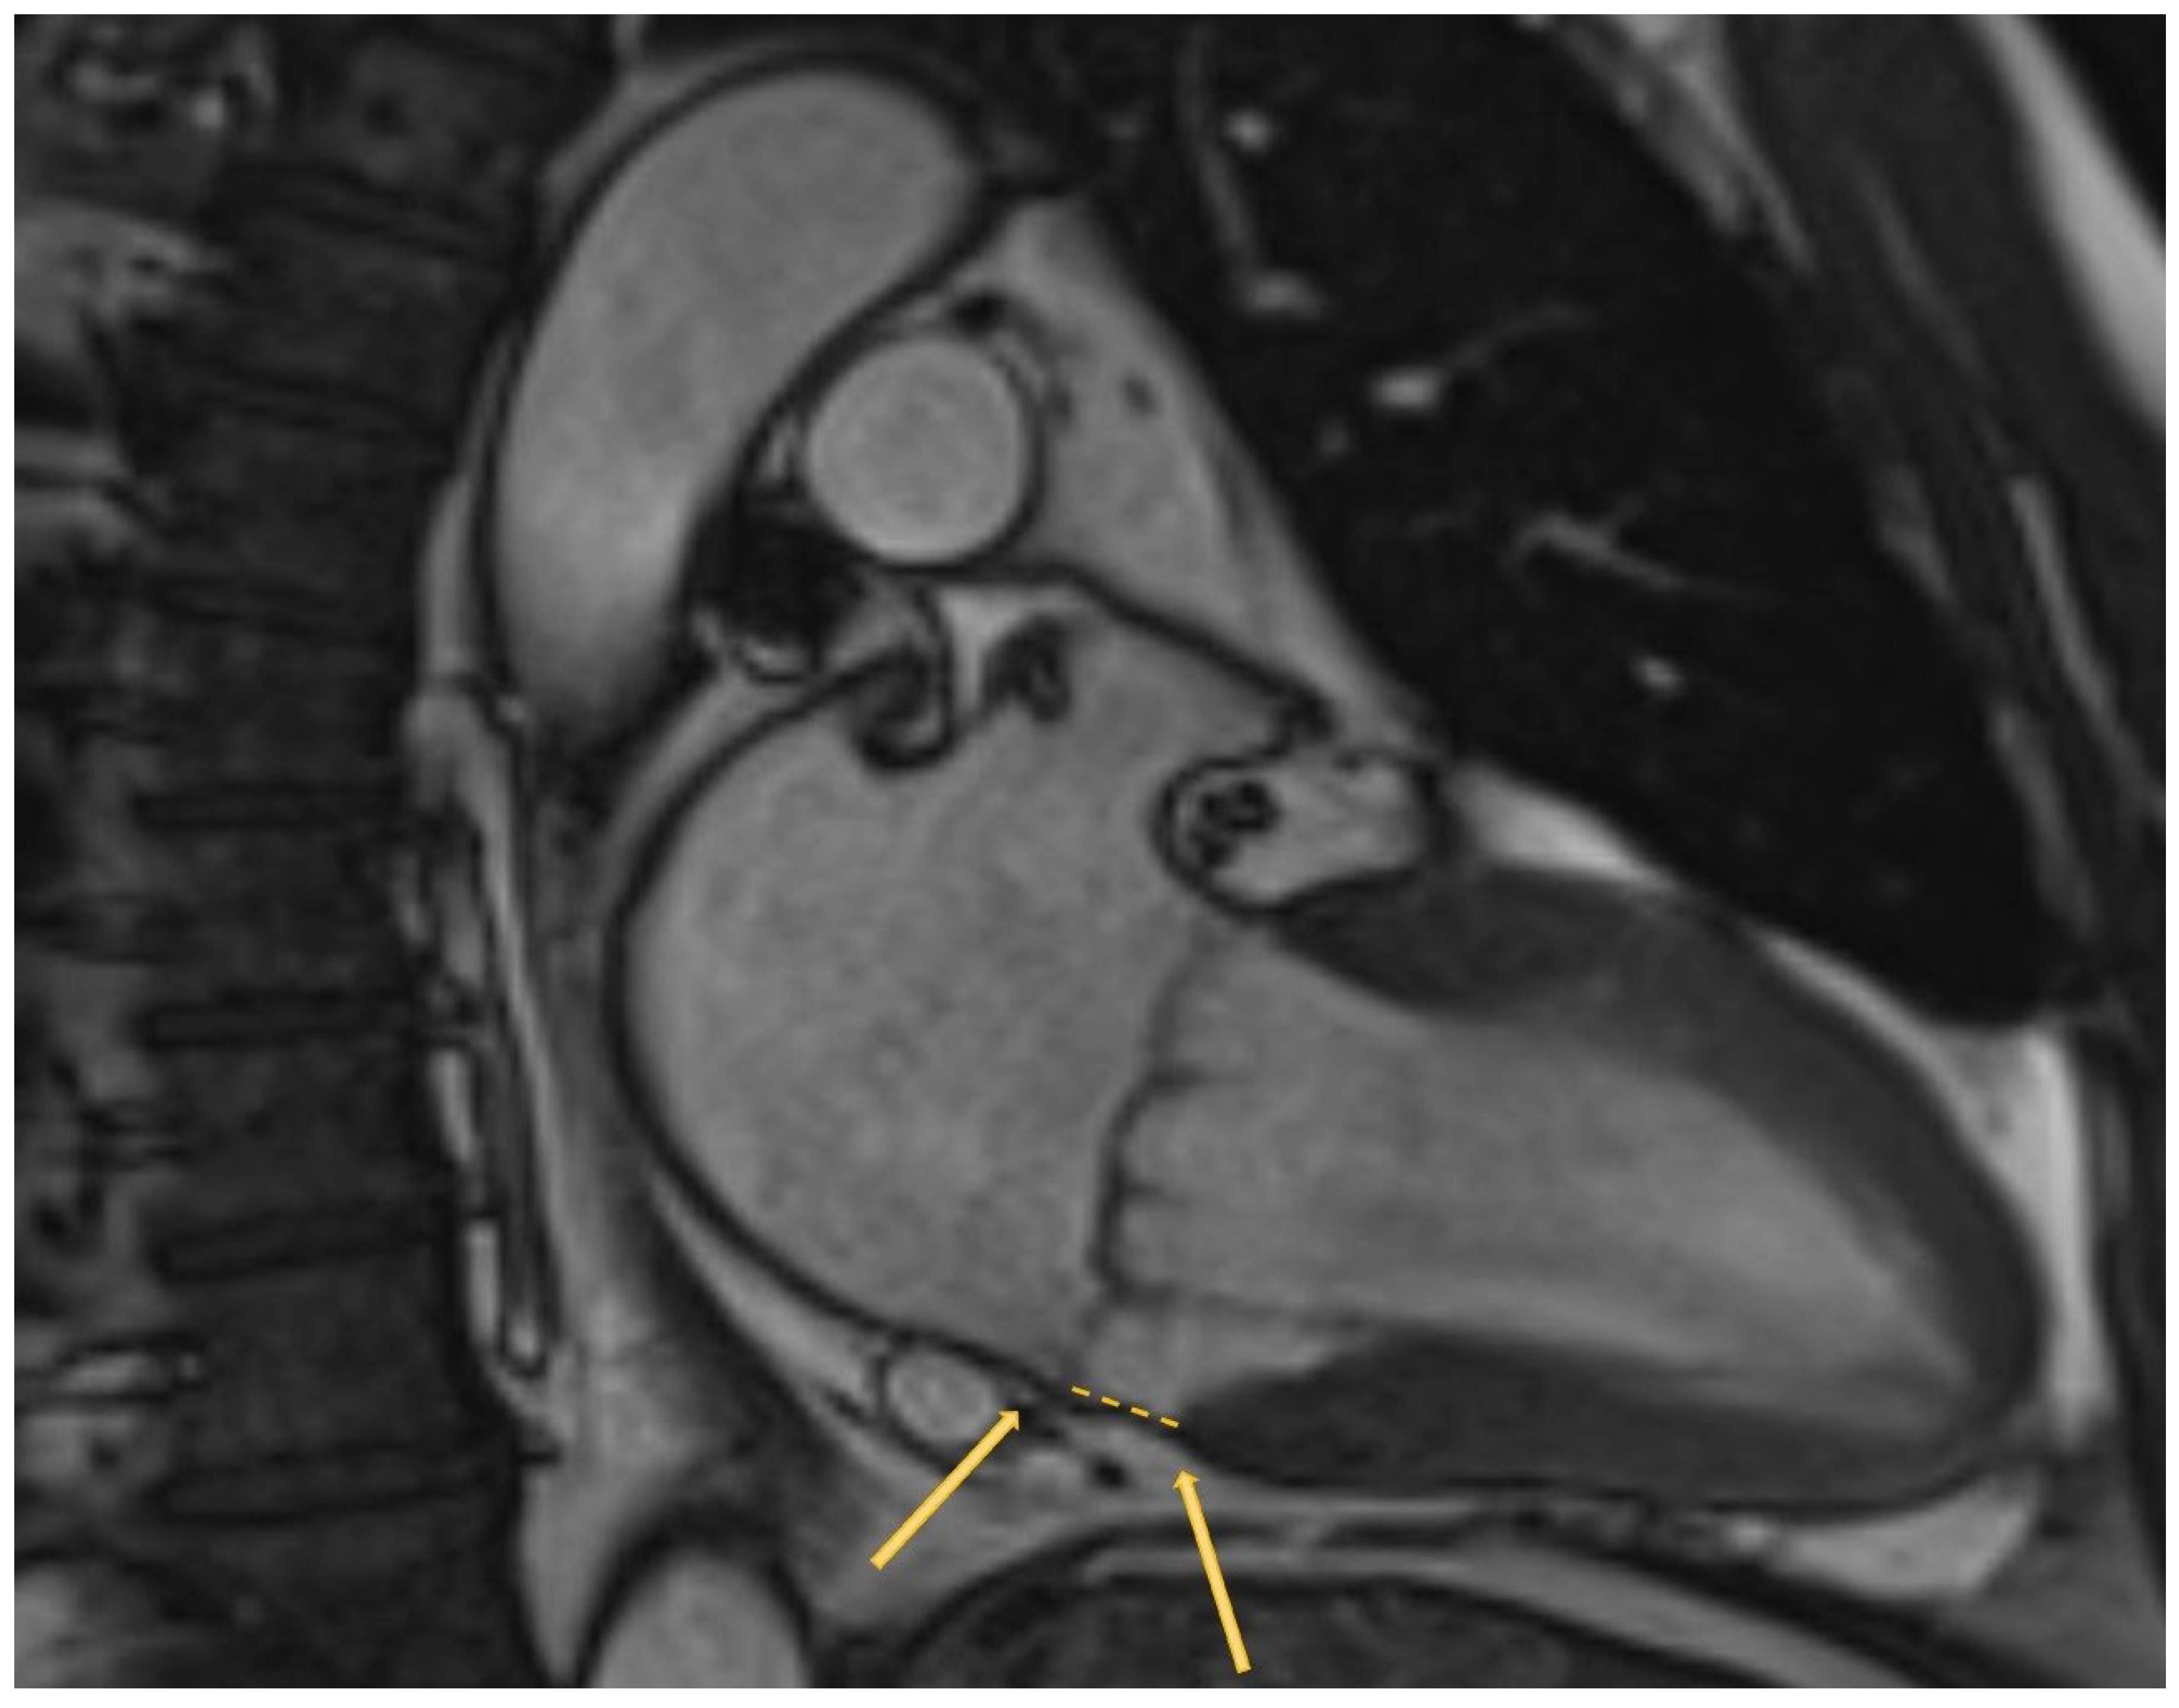

- Dejgaard, L.A.; Lie, O.H.; Helle-Valle, T.M.; Edvardsen, T.; Haugaa, K.H. Reply: Arrhythmic Mitral Annulus Disjunction and Mitral Valve Prolapse: Components of the Same Clinical Spectrum? J. Am. Coll. Cardiol. 2019, 73, 739–740. [Google Scholar] [CrossRef]

- Essayagh, B.; Sabbag, A.; Antoine, C.; Benfari, G.; Batista, R.; Yang, L.T.; Maalouf, J.; Thapa, P.; Asirvatham, S.; Michelena, H.I.; et al. The Mitral Annular Disjunction of Mitral Valve Prolapse: Presentation and Outcome. JACC Cardiovasc. Imaging 2021, 14, 2073–2087. [Google Scholar] [CrossRef]

- Bennett, S.; Thamman, R.; Griffiths, T.; Oxley, C.; Khan, J.N.; Phan, T.; Patwala, A.; Heatlie, G.; Kwok, C.S. Mitral annular disjunction: A systematic review of the literature. Echocardiography 2019, 36, 1549–1558. [Google Scholar] [CrossRef]